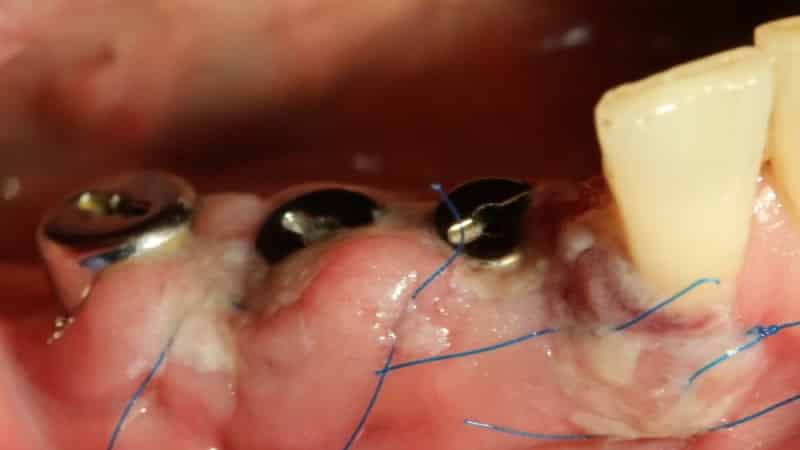

При проведении операции важным аспектом является тактика выполнения вмешательства. Раны заживают успешно только при строгом соблюдении принципов асептики и минимизации травматизации. Атравматическая методика включает в себя последовательность действий, которая предполагает правильный выбор доступа для вмешательства, установку конструкции и закрытие раны.

Установка конструкций

Внедрение импланта осуществляется только после его надежного приживления. Эта процедура выполняется после того, как имплант успешно срастется с костной тканью. Во время операции специалист удаляет специальные заглушки. После выполнения этих действий процедура завершается, и дополнительные вмешательства не требуются.

В процессе восстановления после операции возможны такие проблемы, как кровоизлияния, расхождение швов или воспалительные процессы в области вмешательства. Все это зависит от индивидуальных особенностей организма пациента и его соблюдения рекомендаций врача. Если пациент не будет следовать советам специалиста, риск возникновения осложнений возрастает.

Отторжение имплантата организмом встречается довольно редко и, как правило, связано с воспалительными процессами. Во время операции может произойти перегрев тканей, что приводит к образованию грануляций, мешающих имплантату прижиться. Остеопороз также может стать препятствием для успешной интеграции имплантата, и в таких случаях его удаляют.